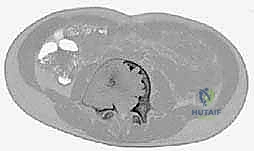

في الـ ABC، يُظهر الرنين المغناطيسي علامة كلاسيكية تُعرف بـ "مستويات السائل-السائل" (Fluid-Fluid Levels)، والتي تنتج عن ترسب خلايا الدم الحمراء وانفصالها عن مصل الدم داخل تجاويف الكيس.

التصوير المقطعي المحوسب (CT Scan):

ممتاز لتقييم سلامة القشرة العظمية بدقة ثلاثية الأبعاد، ويساعد الدكتور هطيف في التخطيط الجراحي وتحديد المناطق التي تحتاج إلى تدعيم ميكانيكي.

صور الرنين المغناطيسي والأشعة المقطعية المتطورة توضح "مستويات السائل-السائل" المميزة لكيس العظم المتمدد، بالإضافة إلى التخطيط الدقيق لحدود الآفة قبل التدخل الجراحي.